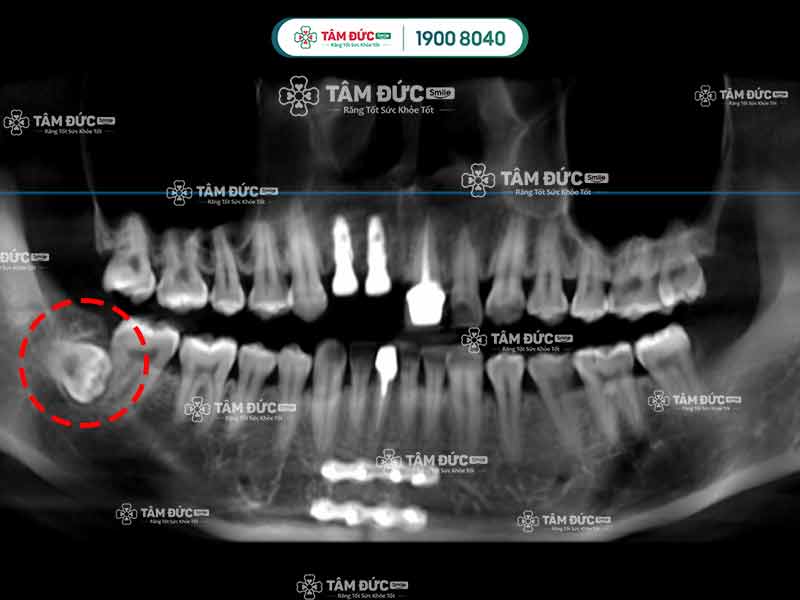

Qua phim X-Quang, Quý khách có thể thấy những chiếc răng mọc ngầm chi chít bên trong xương hàm. Đây là nguyên nhân gây ra những cơn đau nhức vô cớ khi Quý khách ăn nhai, cũng là dấu hiệu răng mọc ngầm cần chú ý. Vậy điều gì dẫn tới hiện tượng răng mọc ngầm?

Răng khôn mọc ngầm đụng trúng răng số 7 kế cận